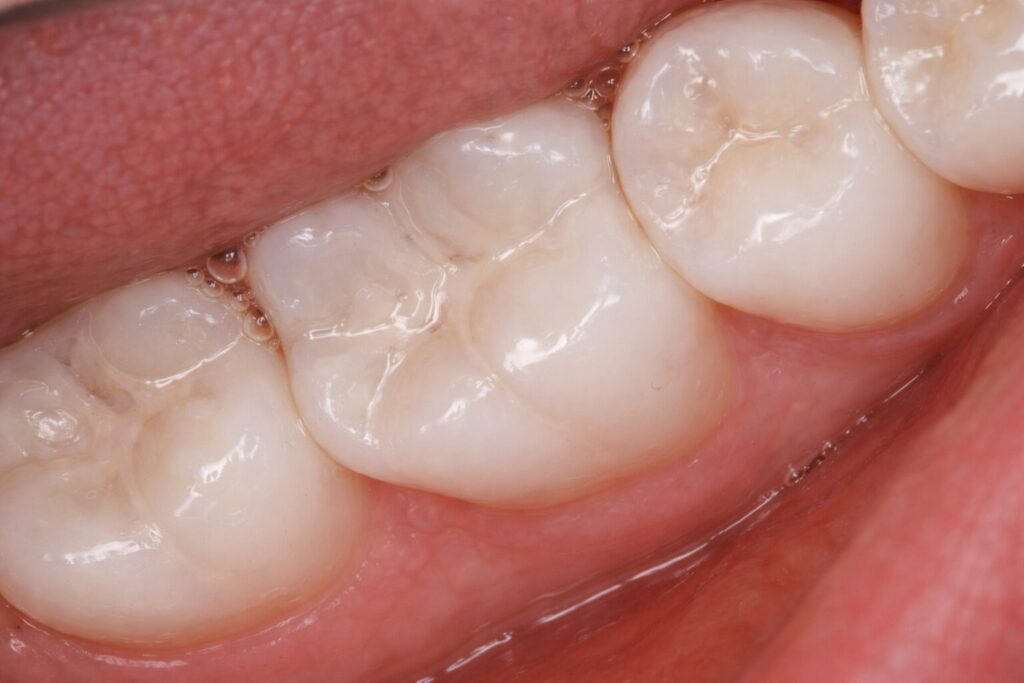

Minimal sealant localized just to the deepest grooves on her molars can be seen, with no excess. Marginal seal even on the 6s was still intact and smooth, with no signs of break down or recurrent decay. A case done right!